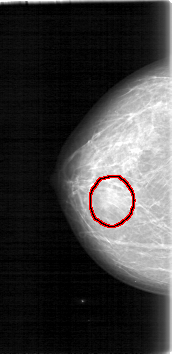

D_4017_1.LEFT_MLO

LEFT_MLO LINES 5326 PIXELS_PER_LINE 2716 BITS_PER_PIXEL 12 RESOLUTION 43.5 NON_OVERLAY

FILE: D_4017_1.RIGHT_CC.OVERLAY

TOTAL_ABNORMALITIES 1

ABNORMALITY 1

LESION_TYPE MASS SHAPE OVAL MARGINS OBSCURED

ASSESSMENT 0

SUBTLETY 3

PATHOLOGY BENIGN

TOTAL_OUTLINES 1

BOUNDARY